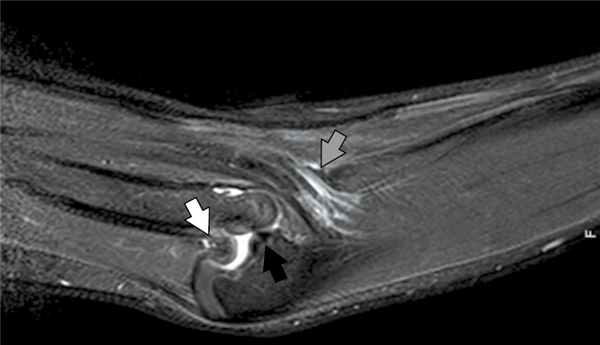

6. Рис. 6. Магнитно-резонансная томограмма правого локтевого сустава. Дупликатура сухожилия трехглавой мышцы плеча (белая стрелка), растянутость сухожилия плечевой мышцы (серая стрелка), подвывих в плечелучевом суставе (черная стрелка)